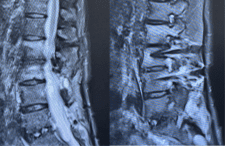

William J. Sonstein, M.D., F.A.C.S. is a Board-Certified Diplomate, American Board of Neurosurgery. He has a special interest in complex spine surgery and has one of the largest experiences with Posterior Lumbar Interbody Fusion (PLIF) on Long Island. This procedure relieves pain for patients with intractable back pain. Dr. Sonstein uses minimally invasive procedures whenever possible, such as Kyphoplasty and X-STOP™ to treat spinal compression fractures and spinal stenosis.

Case Studies